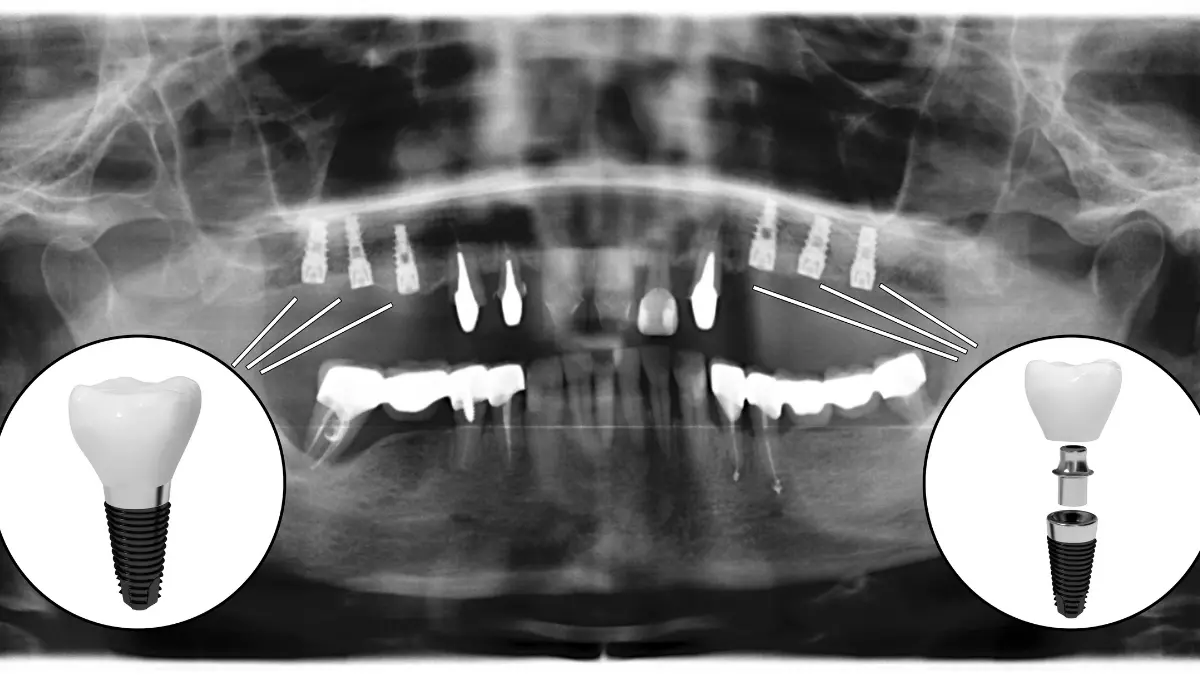

Implant surgery is one of the most effective methods used to treat missing teeth. This process places artificial tooth roots on your teeth, making your teeth look more robust and natural. But for implant surgery, an accurate diagnosis is necessary to fully understand the condition of your teeth. For this reason, dentists often use CBCT scans.

CBCT is an imaging method used by dentists to examine the condition of a patient’s teeth before implant surgery. This method is the digital X-ray technique used by dentists to obtain three-dimensional images.

CBCT scans allow dentists to view your teeth from a 360-degree angle. In this way, a more accurate diagnosis can be made about the condition of your teeth before implant surgery. CBCT scans are used to determine the bone structure of your teeth, the location of nerves, the size of the area where the implant will be placed, and the overall condition of your teeth.

CBCT screening is very important for dentists before implant surgery. Because of these scans, dentists can determine if you are suitable for implant surgery. In addition, CBCT scans also allow dentists to perform procedures more accurately and precisely during implant surgery.